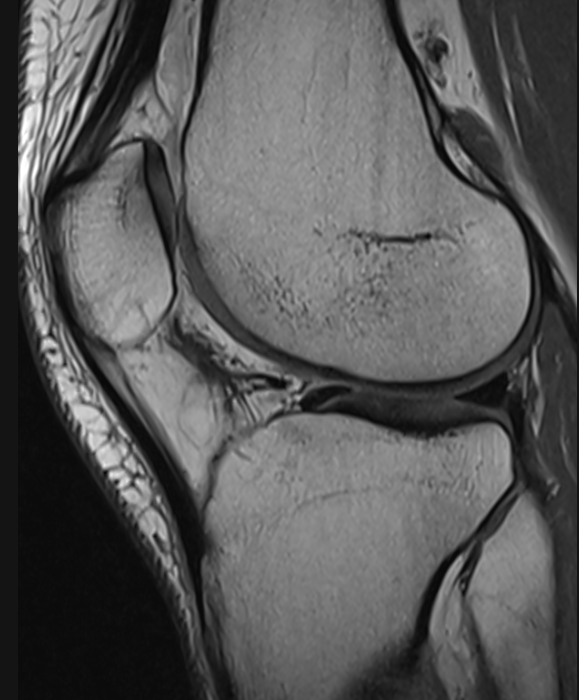

3. Hoffa fat pad scarring post arthroscopy